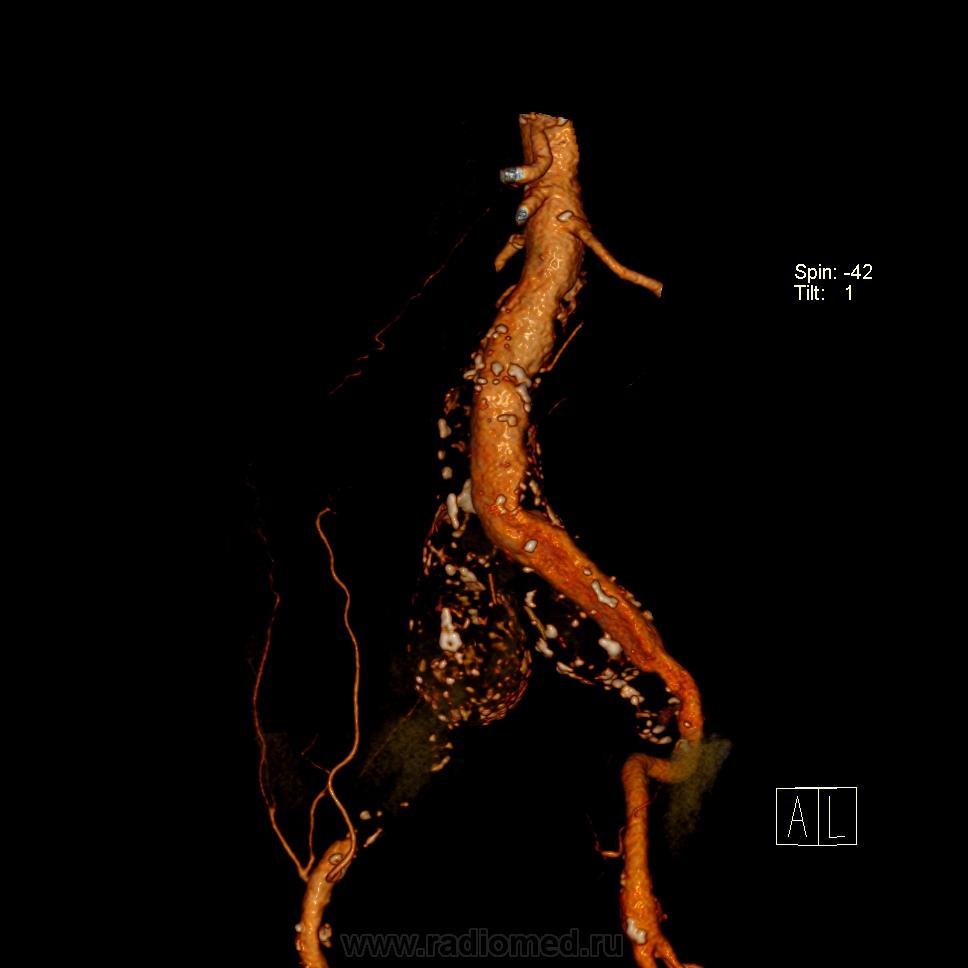

Пациент лежит в кардиологии. Прислали на аортографию. 2 врача УЗИ несколько разошлись в диагнозах: одна видит тромбированную аневризму брюшной аорты, другая - тромбоз нижней полой вены.

А мы получили вот такие красивые картинки.

Шикарно! Тромбированная аневризма инфраренального отдела (над бифуркацией), бифуркации и общих подвздошных артерий, синдром Лериша справа.

И еще маленькая аневризмочка наружной подвздошной слева. Честно говоря, меня больше всего впечатлили коллатерали, благодаря которым клинически он вообще не соответствует исследованию. Конечности теплые, пульсация слабая, но как-то прослеживается...